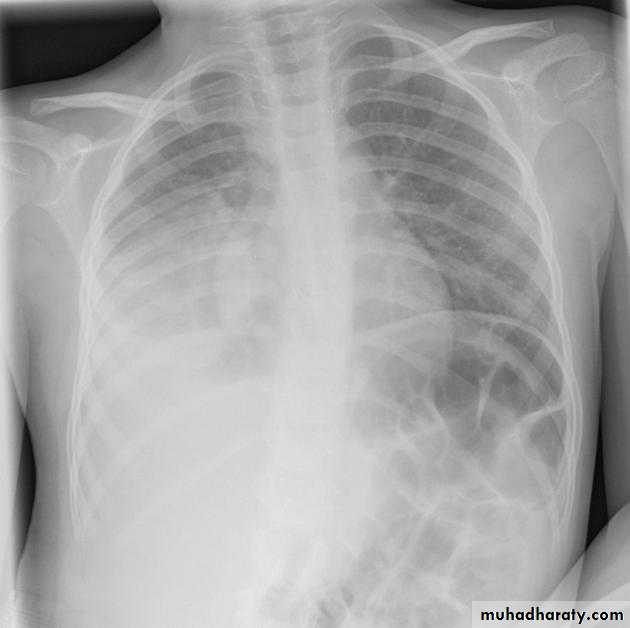

Left upper lobe collapse has distinctive features but can be challenging to identify on chest radiographs by the uninitiated.

Radiographic features

The left upper lobe collapses anteriorly becoming a thin sheet of tissue apposed to the anterior chest wall, and appears as a hazy or veiling opacity extending out from the hilum and fading out inferiorly . It thus reverses the normal slight increase in radiographic density seen as you move down the lung (due to increased thickness of the chest soft tissues).

Parts of the normal cardiomediastinal contour may also be obliterated where the left upper lobe, particularly the lingula abut the left heart border. The anterior parts of the aortic arch are also often obliterated from view.

In some cases the hyperexpanded superior segment of the left lower lobe insinuates itself between the left upper lobe and the superior mediastinum, sharply silhouetting the aortic arch and resulting in a lucency medially. This is known as the luftsichel sign.

The left hilum is also drawn upwards, resulting in an almost horizontal course of the left main bronchus and vertical course of the left lower lobe bronchus.

Non-specific signs indicating left sided atelectasis will also be present, including:

elevation of the hemidiaphragm

'peaked' or 'tented' hemidiaphragm: juxtaphrenic peak sign

crowding of the left sided ribs

shift of the mediastinum to the left

On lateral projections the left lower lobe is hyperexpanded and the oblique fissure displaced anteriorly. There is associated increase in the retrosternal opacity.